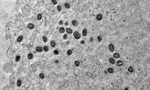

últimas notícias Se ligue! Matrículas da rede municipal já podem ser confirmadas Chegou a "vampirose"! Veja como se curar da virose pós-carnaval Conheça a blogueira que fez influenciador gay se envolver no Carnaval Dois casos de Mpox são registrados na Bahia; saiba os sintomas Desfile inclusivo leva representatividade para passarela em Lauro Boca De Me Dê: empurra, Uber!, espertos, de ressaca e Ana dos Pobres